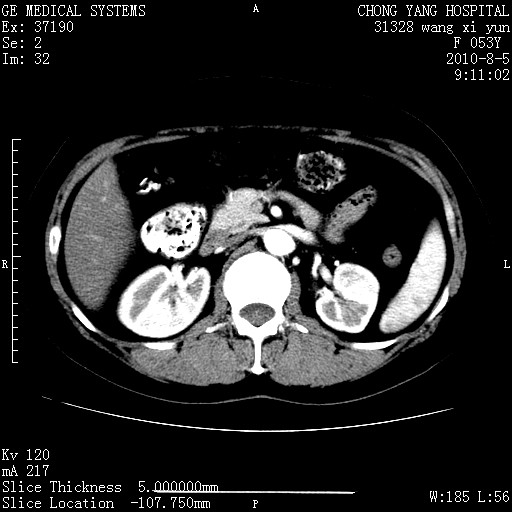

标题: CT28214:F41Y 血尿二十天,建议盆腔平扫加增强。

1)考虑肝左叶胆管细胞癌。2)脂肪肝。